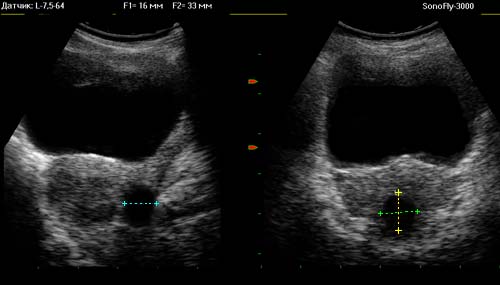

В настоящее время УЗИ женских внутренних половых органов осуществляется с использованием абдоминального и трансвагинального сканирования, которые дополняют друг друга. Аппарат для ультразвуковой диагностики ( УЗИ ) SonoFly-3000 дает возможность использования обоих методов.

Поскольку в гинекологической практике зачастую диагностируются новообразования, в состав программного обеспечения ультразвукового аппарата (УЗИ) SonoFly-3000 включена возможность расчета объемов. Кроме того, можно измерять линейные размеры, площадь и периметр методом эллипса, площадь произвольной области методом обводки.

Наряду с другими методами, аппарат для ультразвуковой диагностики (УЗИ) SonoFly-3000 позволяет проводить построение яркостных гистограмм по любому сканируемому участку. Специфика распределения интенсивности в таких гистограммах помогает судить о природе выявленного образования.

Расчет объема образования по трем размерам

1. Проведение УЗИ - измерений

2. Фиксация в протоколе результатов УЗИ - измерений

3. Наблюдение результата расчета

продольный размер = 9 mm

передне-задний размер = 13 mm

поперечный размер = 10 mm

Объем "A" = 0.6 sm

Обследованы матка и яичники абдоминально. Акустический доступ затруднен, однако исследование возможно. Тело матки расположено обычно. Тело матки не увеличено. Контур тела матки - ровный, четкий. Полость матки не расширена. Яичники не изменены. Обнаружено объемное образование, с выходом за пределы органа. Размеры 9х13х10мм. Объем 0.6мл. Структура кистозная (жидкостная) с нечетко дифференцируемой капсулой.